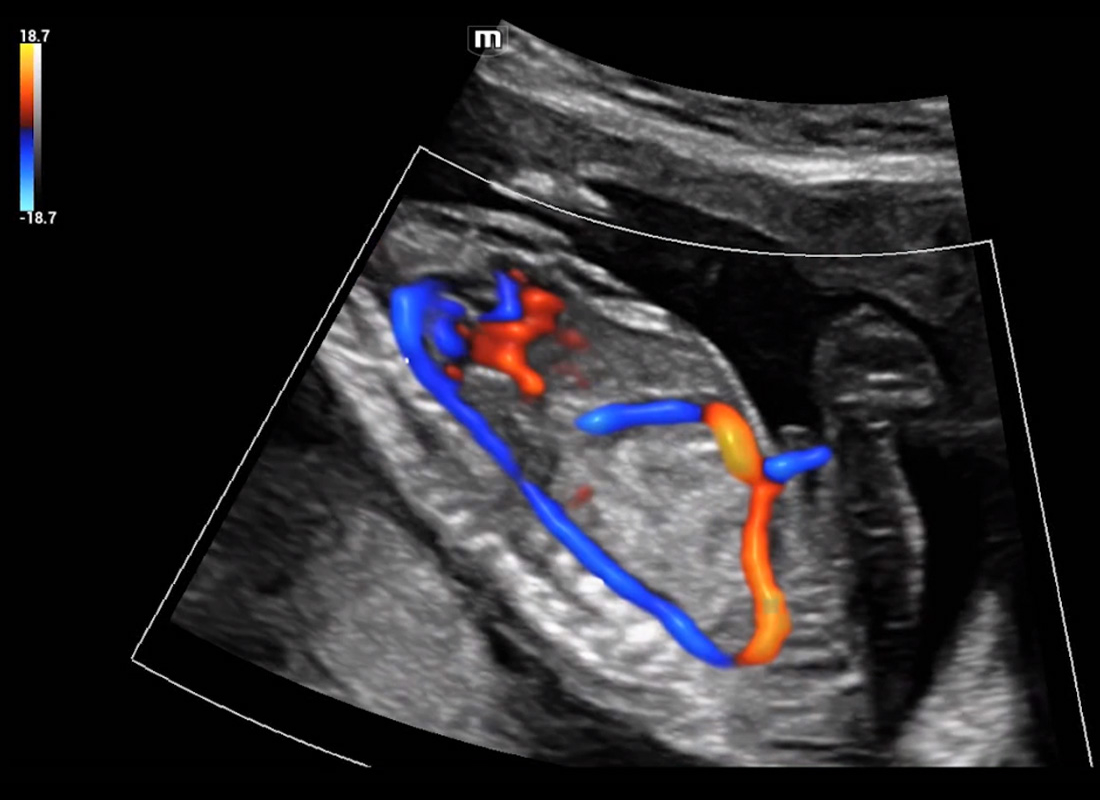

Central nervous system (CNS) malformations are one of the most common congenital abnormalities. Unfortunately, due to imaging limitations such as poor fetal position, acoustic shadowing, and operatorsŌĆÖ poor scanning skills, the MSP is particularly difficult to find in a 2D ultrasound. In this case, a faster and more user-friendly method, which automatically displays the standard planes together with the required measurements in a fetal CNS examination, could significantly boost both the quality and efficiency of clinical diagnoses.?NuewaŌĆÖs intelligent solution of fetal brain can realize automatic acquisition of brain volume data based on intelligent recognition of CNS application scenarios, intelligent generation of four fetal brain standard planes including MSP, automatic measurement of CNS biological items and automatic evaluation of fetal brain volume. More importantly, Nuewa's leading color Doppler technology can provide a clear and sensitive dynamic display of blood flow in the tiny vessels.